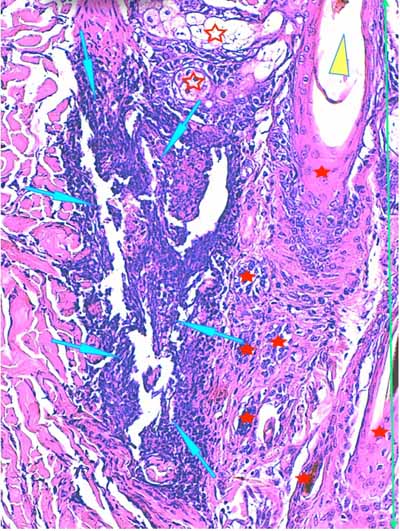

Photo 13 (Hémalun-Eosine X200) : dans le derme, on remarque des plages

cellulaires inflammatoires, peuplées de granulocytes neutrophiles,

en étroit rapport avec les unités annxielles folliculo-sébacées.

Légendes de la Photo 13 :

- Étoiles rouges vides : glandes sébacées

- Étoiles rouges pleines : follicules pileux

- Pointe de flèche jaune : canal pilaire

- Flèches turquoises : plage cellulaire inflammatoire peuplée de cellules pycnotiques et de granulocytes neutrophiles

- Double flèche verte : derme

Photo 14 (Hémalun-Eosine X100) : à la jonction dermo-hypodermique,

un bulbe folliculaire anormal est en rapport direct avec une plage cellulaire inflammatoire.

Légendes de la Photo 14 :

- Étoile rouge vide : adipocyte

- Étoiles rouges pleines : vaisseaux sanguins (une erreur au milieu à droite = adipocyte)

- Pointe de flèche jaune : reliquat de bulbe pilaire fracturé et désolidarisé du reste du follicule pileux

- Flèches turquoises : plage cellulaire inflammatoire peuplée de cellules pycnotiques et de granulocytes neutrophiles, en étroit rapport avec le reliquat de bulbe folliculaire

- Double flèche bleue : hypoderme